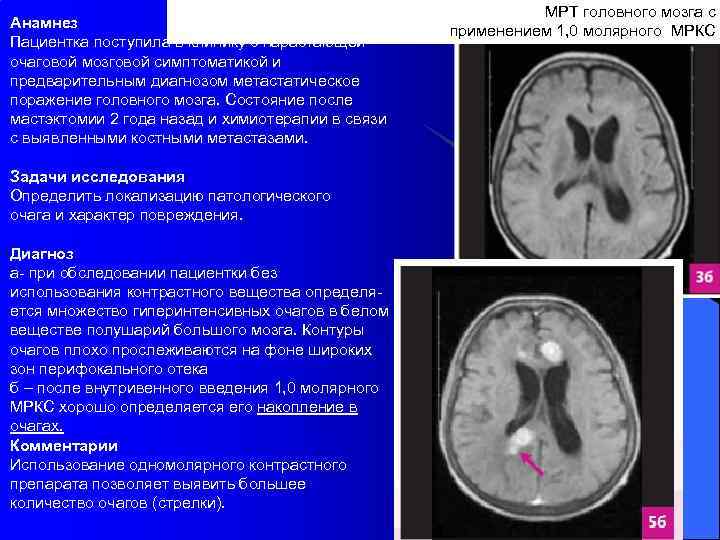

Анамнез Пациентка поступила в клинику с нарастающей очаговой мозговой симптоматикой и предварительным диагнозом метастатическое поражение головного мозга. Состояние после мастэктомии 2 года назад и химиотерапии в связи с выявленными костными метастазами. Задачи исследования Определить локализацию патологического очага и характер повреждения. Диагноз а- при обследовании пациентки без использования контрастного вещества определяется множество гиперинтенсивных очагов в белом веществе полушарий большого мозга. Контуры очагов плохо прослеживаются на фоне широких зон перифокального отека б – после внутривенного введения 1, 0 молярного МРКС хорошо определяется его накопление в очагах. Комментарии Использование одномолярного контрастного препарата позволяет выявить большее количество очагов (стрелки). МРТ головного мозга с применением 1, 0 молярного МРКС